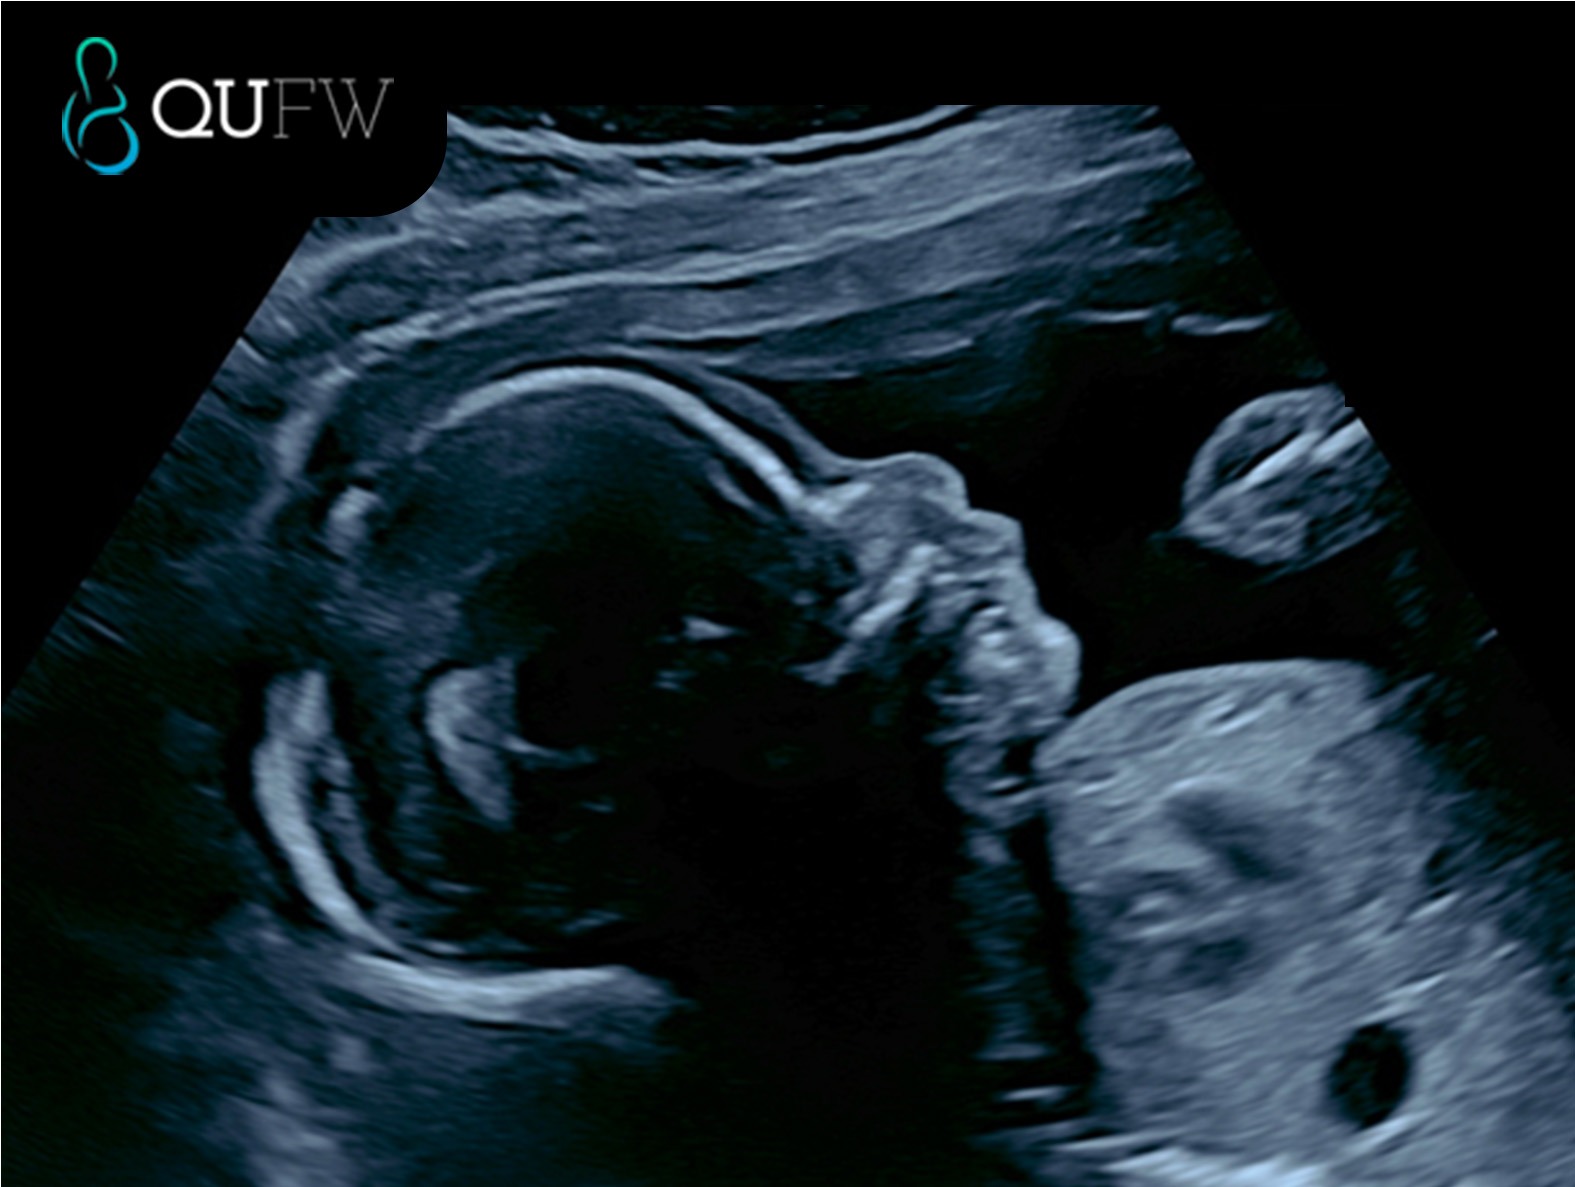

The morphology, or 20 week scan, is performed to assess structure and development of the baby, the position of the placenta, the growth of the baby, and the amount of amniotic fluid surrounding the baby.

The examination is performed by one of our highly trained obstetric sonographers using state of the art ultrasound equipment. The scan includes a detailed examination of the developmental anatomy of the baby’s heart, kidneys, brain, face, stomach, lungs, spine, abdomen, arms, legs, hands and feet.

Measurements of the head, abdomen, arms and legs are taken to review/estimate gestational age. At this stage the baby is now too big to measure the entire length from head to toe. The amniotic fluid, your cervix and the placenta location will also be assessed.